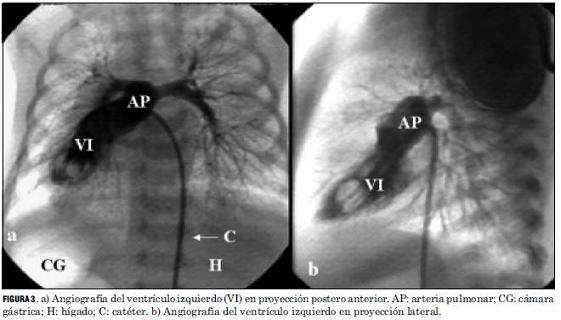

El análisis anatómico destaca que 40 pacientes presentaron D-TGA con séptum interventricular intacto y 20 con comunicación interventricular. Uno de estos pacientes asoció una coartación de aorta con severa hipoplasia del arco aórtico, otro era portador de un situs inversus (figuras 2 y 3), y otro presentaba una estenosis subpulmonar leve (tabla 4, figura 4).